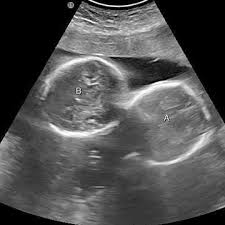

इंदौर। इंदौर के ESIC अस्पताल से प्रेगनेंसी का एक बेहद चौंकाने वाला मामला सामने आया है. यहां पर एक महिला ने तीन बच्चों को जन्म दिया. इससे भी ज्यादा हैरान कर देने वाली ये है कि जब डॉक्टर ने डिलीवरी से पहले अल्ट्रासाउंड किया था तब रिपोर्ट में दो बच्चे ही दिख रहे थे. लेकिन जब महिला ने तीन बच्चों को जन्म दिया तो डॉक्टर भी हैरान रह गए।

हॉस्पिटल के डॉक्टरों का मानना है कि ऐसे केस मेडिकल फील्ड के रेयर केसेस में से एक होते हैं. महिला ने 1 बेटा और 2 बेटियों को जन्म दिया है. अधिकारी ने बताया कि कर्मचारी राज्य बीमा निगम (ईएसआईसी) के चिकित्सा महाविद्यालय से जुड़े अस्पताल में 27 वर्षीय महिला ने दो लड़कियों और एक लड़के को रविवार (29 मार्च) को सामान्य तरीके से जन्म दिया. इस प्रसव के बाद जच्चा व तीनों नवजात शिशु स्वस्थ हैं।